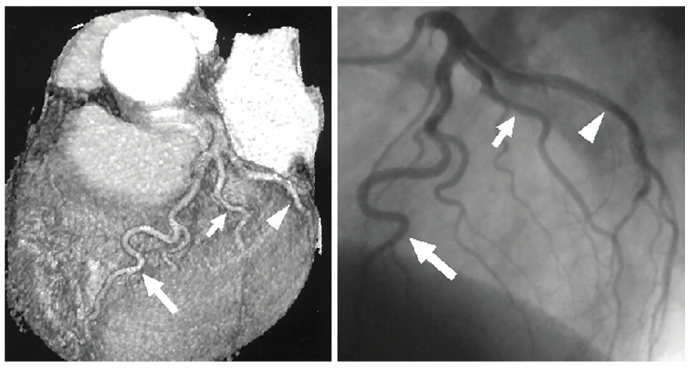

Coronary anatomy (Figure 9) can be demonstrated non-invasively by computerized tomography (CTA) or invasively by contrast catheter cannulation techniques. Recall that CTA is a 3-dimensional representation of the arteries, the vessel walls and lumina, and the surrounding structures. In contrast, contrast catheter angiography is a 2-dimensional image or lumenograms showing the artery in a single plane without vessel wall detail. Coronary angiography requires multiple views to define the course of the vessels.

The names of coronary branch anatomy are straightforward. The left coronary artery (Figure 10A) has 7 named branches; the left main trunk gives rise to the left anterior descending (LAD) and circumflex (Cx) arteries. Subbranches from the LAD are the septals and diagonals. The circumflex subbranches run transversely to the margin of the heart, hence the name, obtuse marginals.

The right coronary artery branches are named after structures supplied (Figure 10B). Beginning at the sinus of Valsalva, the sinoatrial branch runs posteriorly to the top of the right atrium and the conus artery runs anteriorly over the pulmonary outflow tract. Along the course of the right coronary artery (RCA), marginal branches supply the anterior aspect of the right ventricle. On the bottom of the heart, the RCA branches into the posterior descending, running the inferior intraventricular groove, and the posterior lateral branches, supplying the inferior lateral wall.